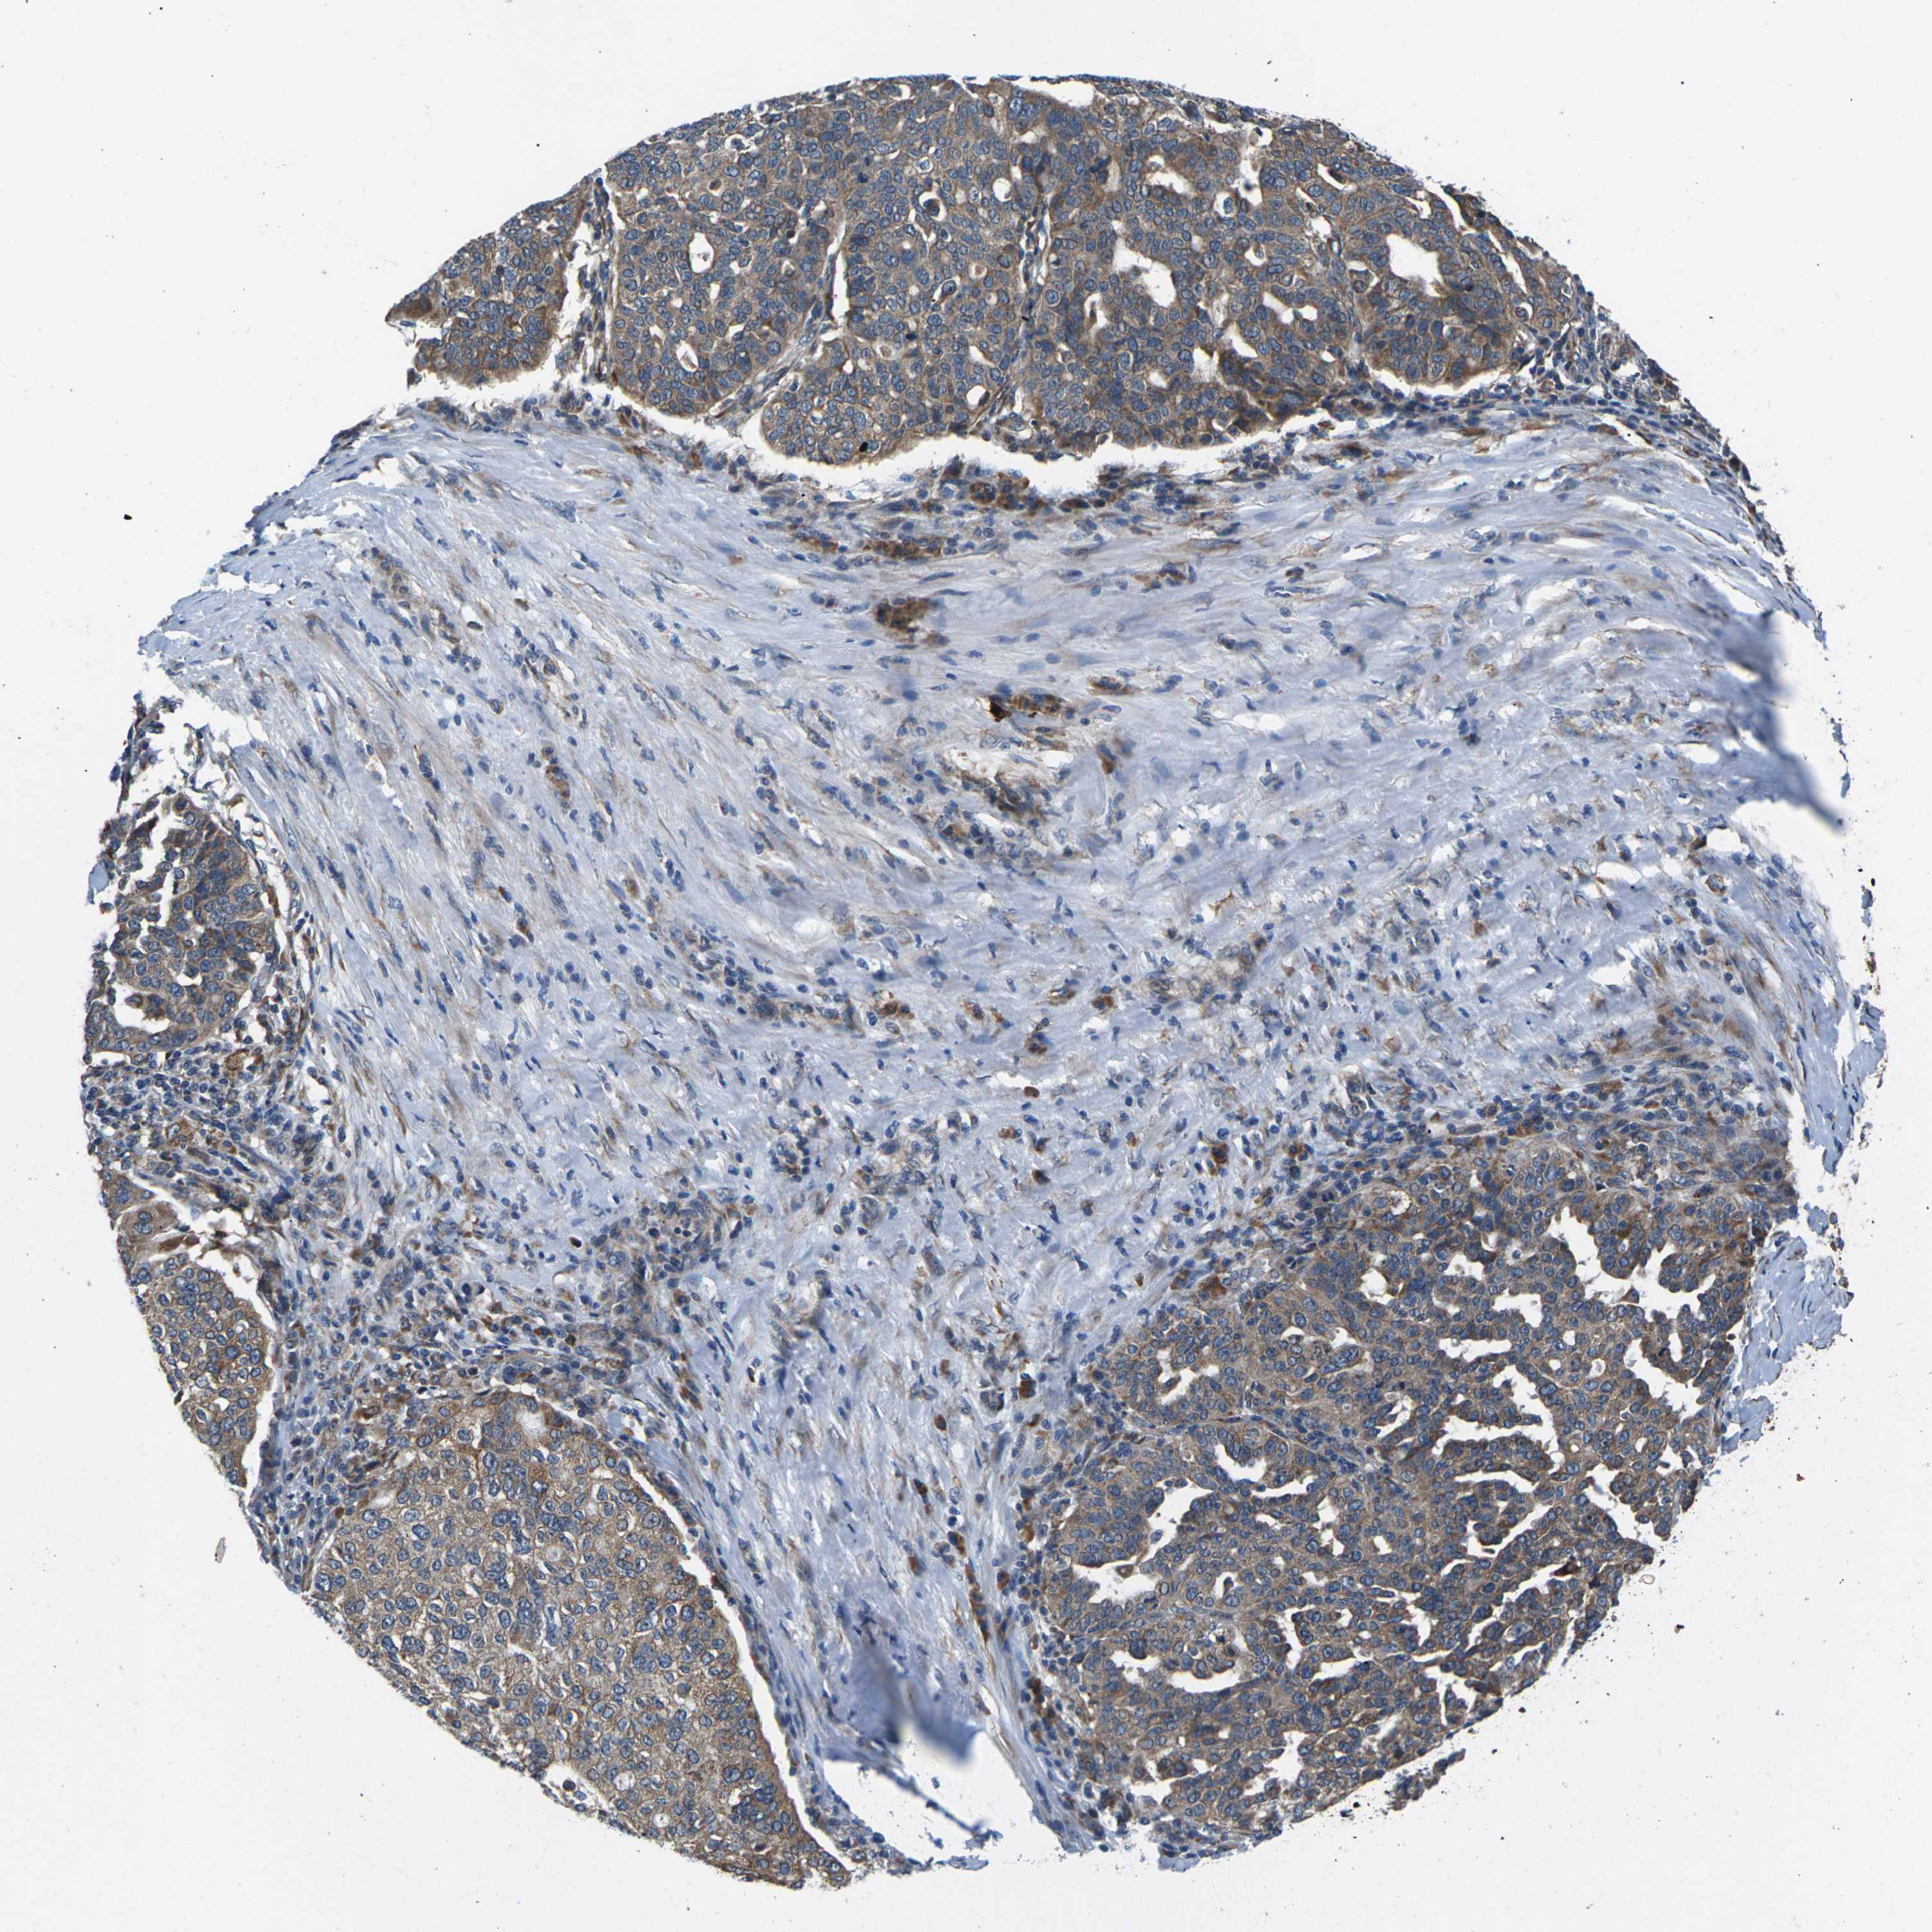

OVARIAN CANCER - Protein expressioni

A mouse-over function shows sample information and annotation data. Click on an image to view it in a full screen mode. Samples can be filtered based on level of antibody staining by selecting one or several of the following categories: high, medium, low and not detected. The assay and annotation is described here.

Note that samples used for immunohistochemistry by the Human Protein Atlas do not correspond to samples in the TCGA dataset.

Antibody stainingi

Antibody staining in the annotated cell types in the current human tissue is reported as not detected, low, medium, or high, based on conventional immunohistochemistry profiling in selected tissues. This score is based on the combination of the staining intensity and fraction of stained cells.

Each image is clickable and will lead to virtual microscopy that enables deeper exploration of all samples and also displays staining intensity scores, fraction scores and subcellular localization as well as patient and tissue information for each sample.

Antibody CAB014883

Staining

High

Medium

Low

Not detected

Intensity

Strong

Moderate

Weak

Negative

Quantity

>75%

75%-25%

<25%

None

Location

Nuclear

Cytoplasmic/membranous

Cytoplasmic/membranous,nuclear

Cystadenocarcinoma, serous, NOS

Carcinoma, endometroid

Cystadenocarcinoma, mucinous, NOS

Carcinoma, NOS